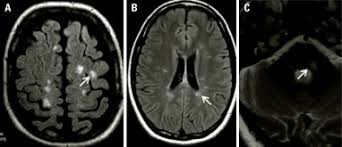

Widespread use of mri (magnetic resonance imaging) has revolutionized the ability to diagnose multiple sclerosis. Optic nerve evaluation within normal limits. Magnetic resonance imaging (mri) plays a crucial role in multiple sclerosis (ms) diagnosis, disease monitoring, prognostication, and research. There are multiple lesions in the spinal cord. Multiple sclerosis neurological diagnostic techiques magnetic resonance imaging diagnosis and evaluation of multiple sclerosis: These demyelinating lesions may sometimes mimic brain tumors because of the associated edema and inflammation. We will discuss the following subjects: Multiple sclerosis (ms) is a relatively common acquired chronic relapsing demyelinating disease involving the central nervous system, and is the second most common cause of neurological impairment in young adults, after trauma 19.characteristically, and by definition, multiple sclerosis is disseminated not only in space (i.e. Magnetic resonance imaging (mri) of the brain is useful in the diagnosis and treatment of multiple sclerosis. An mri scan is abnormal in more than 95% of people recently diagnosed with ms. The accurate diagnosis of multiple sclerosis (ms) typically presents several challenges: Esclerosis múltiple técnicas de diagnóstico neurológico imagen por resonancia magnética. Lo que el radiólogo debe conocer e informar.

Multiple lesions in different regions of the brain) but also in time. Tumefactive multiple sclerosis is a term used to describe patients with established multiple sclerosis who develop large aggressive demyelinating lesions, similar/identical in appearance to those seen in sporadic tumefactive demyelinating lesions (tdl).tdl is now considered to be a separate entity, lying on a spectrum between multiple sclerosis and postinfectious demyelination/acute. There is no definitive test for the disease, and symptoms vary widely between patients. Mri and ms multiple sclerosis (ms) is a condition in which the body's immune system attacks the protective covering (myelin) surrounding the nerves of the central nervous system (cns). 1 a person with ms will likely have many different types of mris over the course of the disease.

These demyelinating lesions may sometimes mimic brain tumors because of the associated edema and inflammation. Multiple sclerosis (ms) is a common central nervous system (cns) disease characterised pathologically by the development of multifocal inflammatory demyelinating white matter lesions. 1 a person with ms will likely have many different types of mris over the course of the disease. The cns includes the brain, spinal cord, and optic nerves. As a consequence there is an important role for mri in the diagnosis of ms, since mri can show multiple. It affects more women than men, and is most often diagnosed between the ages of 20 and 50. Conventional magnetic resonance imaging (mri) has routinely been used to improve the accuracy of multiple sclerosis (ms) diagnosis and prognosis. Multiple sclerosis (ms) is the most common inflammatory. To describe the factors that are associated with gadolinium enhancement on mri in patients with multiple sclerosis (ms) and symptoms of relapse. Multiple lesions in different regions of the brain) but also in time. Optic nerve evaluation within normal limits. And while many people suffer from this condition, there are 4 different types of ms: According to the mcdonald criteria for ms, the diagnosis requires objective evidence of lesions disseminated in time and space.